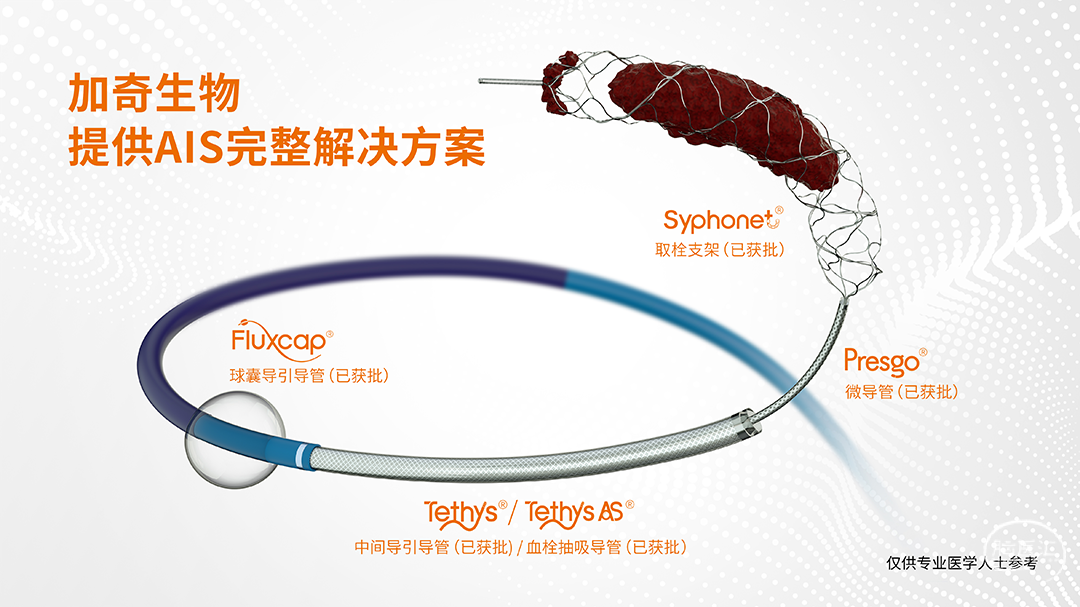

BASIS技术与COSIS技术均是基于加奇生物自主研发的Syphonet®取栓支架为基础衍生出的优化手术流程的新技术,其核心在于Syphonet®取栓支架0.0154in的输送导丝可以匹配球囊进行球囊扩张、部分支架系统释放等。基于BASIS/COSIS技术的应用体会,我们认为Syphonet®取栓支架也可以作为远端锚定导丝,进行颅内狭窄/闭塞的开通,在远端Syphonet®取栓支架的锚定下,利用输送导丝作为工作导丝,进行一系列操作。其优势在于:

· 8F 导引导管

· 6F 中间导管

· 加奇生物 4.0*30mm Syphonet®取栓支架

· XT-17微导管

· 球囊 2.0*15mm

· 0.14inch 200cm 微导丝

· PLUS微导管

· 自膨式支架